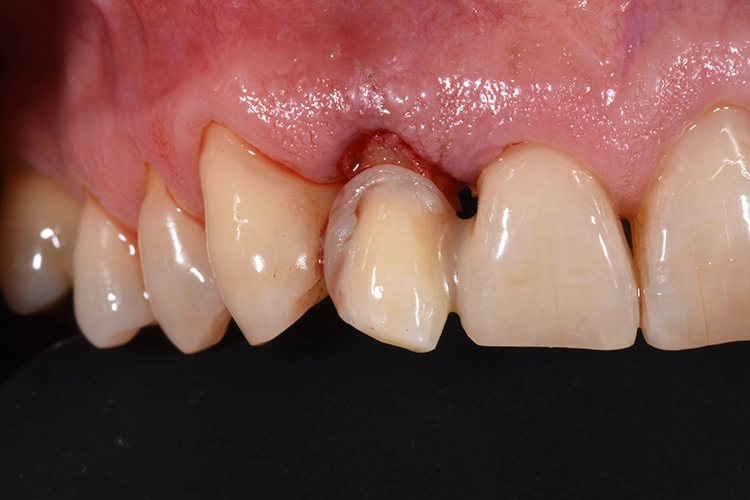

Hieraus ergibt sich, dass bei Jugendlichen und jungen Erwachsenen eine implantologische Behandlung im ästhetischen Bereich möglichst lange herausgeschoben oder vermieden werden sollte, die Suche nach Alternativen zum Zahnimplantat ist naheliegend [5]. Subgingivale Defekte gelten schnell als nicht restaurierbar und die Zähne somit als nicht erhaltungswürdig.

Zahlreiche Studien bestätigen den Gedanken, dass ein ausreichendes Ferrule Design für die Langzeitstabilität eines überkronten Zahnes von ausschlaggebender Bedeutung ist. Es sollten mindestens 2-3 mm des eigenen Zahnes durch die Präparation gefasst sein [6].

Um das bei tief koronal oder subgingival frakturierten Zähnen erreichen zu können, bieten sich dem Behandler verschiedene Möglichkeiten. Zum einen kann durch eine chirurgische Kronenverlängerung Zahnhartsubstanz freigelegt werden, wobei man hier in aller Regel mit einem deutlichen Verlust der Ästhetik rechnen muss, vor allem wenn es sich um eine unilaterale Therapie handelt [7]. Eine Alternative ist die Extrusion des Zahnes aus der Alveole, hierbei werden in der Literatur sowohl die kieferorthopädische Extrusion als auch die intraalveoläre Transplantation beschrieben [8].